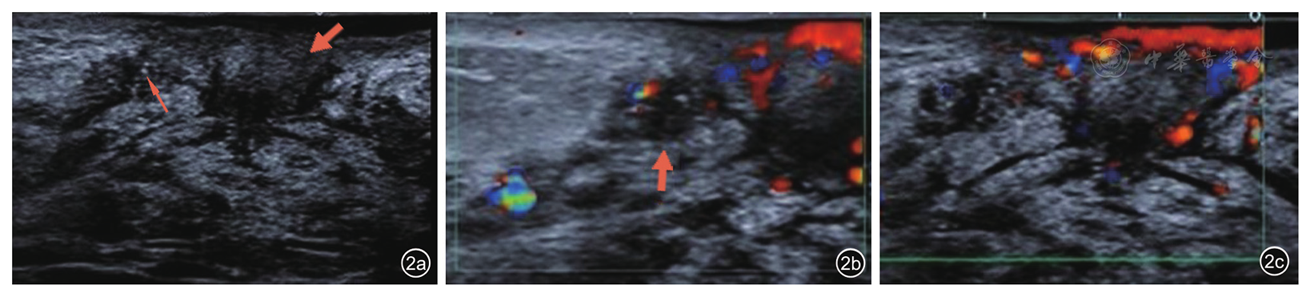

图2 左乳病变区超声声像图。图a左乳晕中央区低回声结节(粗箭头);左乳低回声低回声结节,边界不清,内见砂砾样钙化(细箭头);图b彩色多普勒于左乳低回声结节内探及短线状血流信号;图c彩色多普勒于左乳晕中央区低回声结节内探及较丰富血流信号